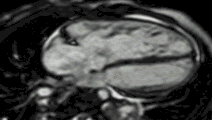

- ↑ "Case of the Week Number 06-01. Left Atrial Myxoma". Society for Cardiovascular Magnetic Resonance. 2016-10-21. Archived from the original on 2009-01-16. Retrieved 2016-12-02.